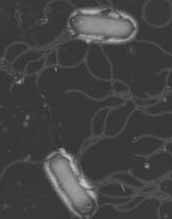

「大腸菌O157」は、大腸菌のうちO抗原が157番目でH抗原が7の場合、「大腸菌O157:H7」と表現されます。

一般に「腸管出血性大腸菌O157」と呼ばれていましたが、現在では「ベロ毒素産生性大腸菌 O157」とも呼ばれています。